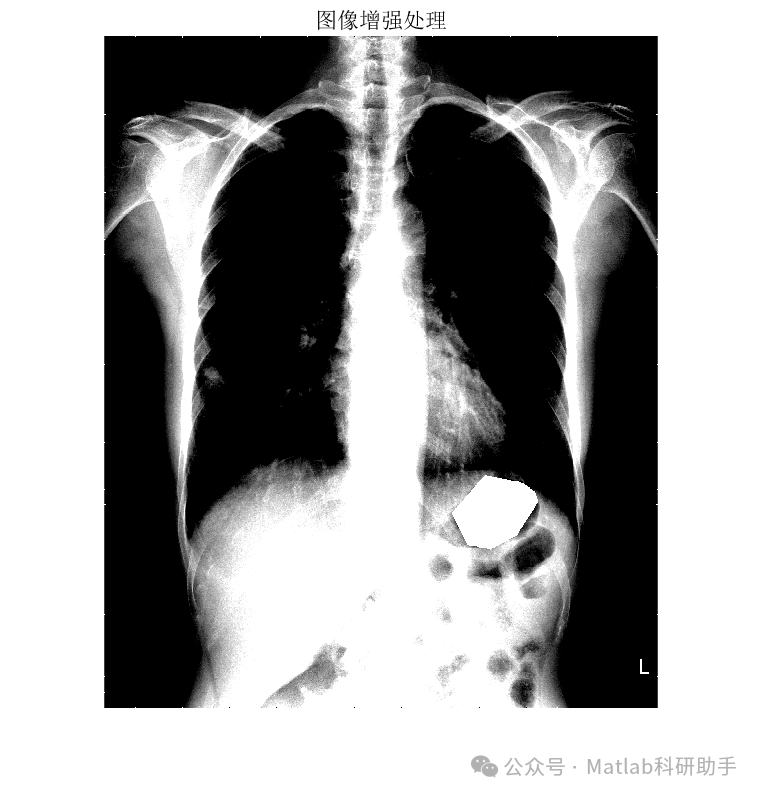

基于最小误差法的胸片分割系统,通常采用深度学习模型,如U-Net或其变体,作为核心分割引擎。该模型通过大量标注数据进行训练,学习从胸片图像到肺部区域掩膜的映射关系。其核心思想是最小化模型预测的分割结果与真实标注之间的误差,从而实现准确的分割。

具体的训练过程中,常用的损失函数包括Dice Loss和Binary Cross Entropy Loss等。Dice Loss关注分割区域的重叠度,更适用于解决类别不平衡问题。Binary Cross Entropy Loss则逐像素地比较预测概率和真实标签,适用于像素级别的分割任务。通过选择合适的损失函数并优化模型参数,能够有效降低分割误差,提高分割精度。